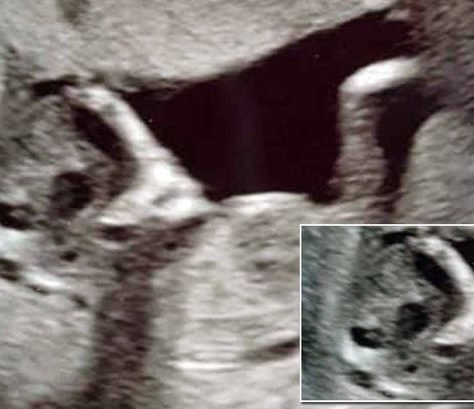

Gëzimi që mbante në bark një

Në qershor, moderatorja e njohur Floriana

Gjira Kajtazi është bërë mama për

Thashethemet për shtatzëninë e Irës, bashkëshortes

Lajmi i cili u dha nga

Amy Schumer, e cila u bë